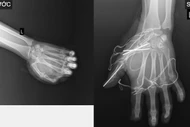

Một bé trai 15 tuổi ở Nghệ An bị lưỡi câu móc sâu vào mặt trong lúc câu cá, được cấp cứu kịp thời để tránh tổn thương nặng.